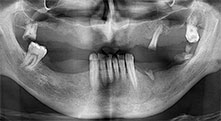

Брату: Ние използваме инструментите за събиране на костни блокове и разделяне на алвеоларни гребени. Ние също използваме Piezomed B6/B7 за остеотомия на наранени зъби и отстраняване на неуспешни импланти. Всички индикации, които изискват дълбоки, чисти разрези.

Брату: Ние предпочитаме да събираме кост от външната страна на гребена в задната част на долната челюст. След разрязване на меките тъкани, ние използваме новите триони, за да определим количеството кост, което ще събираме. С този подход, ние използваме трионите за цялата препарация в почти 80% от случаите. Може да използваме и други пиезо инструменти и накрая длето за мобилизиране на блока. Ние смятаме, че това е изключително ефективна хирургична техника.

Брату: Ние предпочитаме да използваме техниката "сандвич" за аугментация в страничната долна челюст. Покритие на костта се подготвя с пиезо трион и кресталният фрагмент се фиксира с микровинтове. Поставяме смес от автогенна костна присадка и ксеногенен костозаместител между тях. Това работи много надеждно. Трябва винаги да осигурявате достатъчно оразмерени вертикални срезове при шиниране на алвеоларния гребен в долната челюст. В противен случай, костта лесно може да бъде счупена.